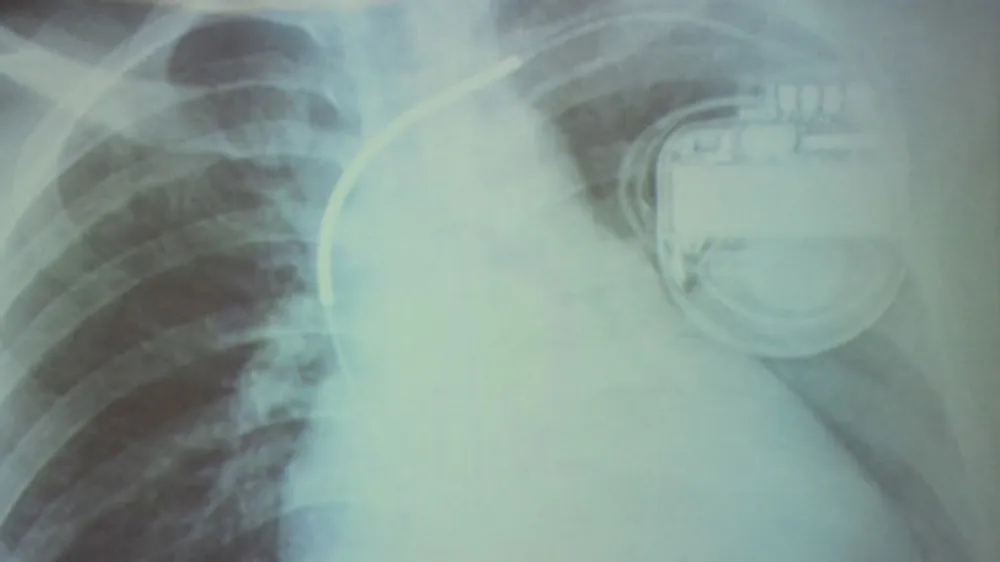

Cứu sống bệnh nhân bị loạn nhịp tim hiếm gặp ảnh 1 Hình ảnh cho thấy bệnh nhân đã được cài máy phá rung

Tại đây, qua kiểm tra, các bác sĩ phát hiện bệnh nhân bị yếu cơ tim thất phải gây loạn nhịp tim (250 lần). Bệnh này có thể dẫn đến ngất xỉu, đột tử bất cứ lúc nào. Các bác sĩ đã điều trị nội khoa kèm cấy vĩnh viễn vào người bệnh máy tạo nhịp tim để xung điện điều chỉnh nhịp tim, dự phòng những bất trắc sức khỏe có thể xảy đến.